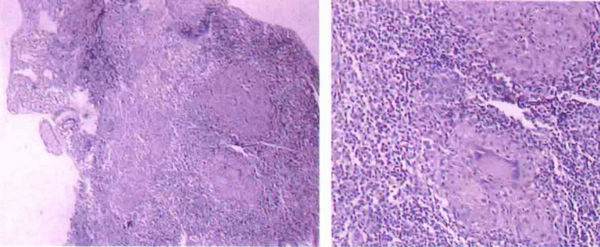

性病淋巴肉芽肿又称腹股沟淋巴肉芽肿或第四性病,与梅毒、淋病和软下疳统称为经典性病。淋巴肉芽肿又称

性病淋巴肉芽肿图片是什么样子的?很多朋友对于性病性淋巴肉芽肿图都表示甚感兴趣。性病性淋巴肉芽肿,其